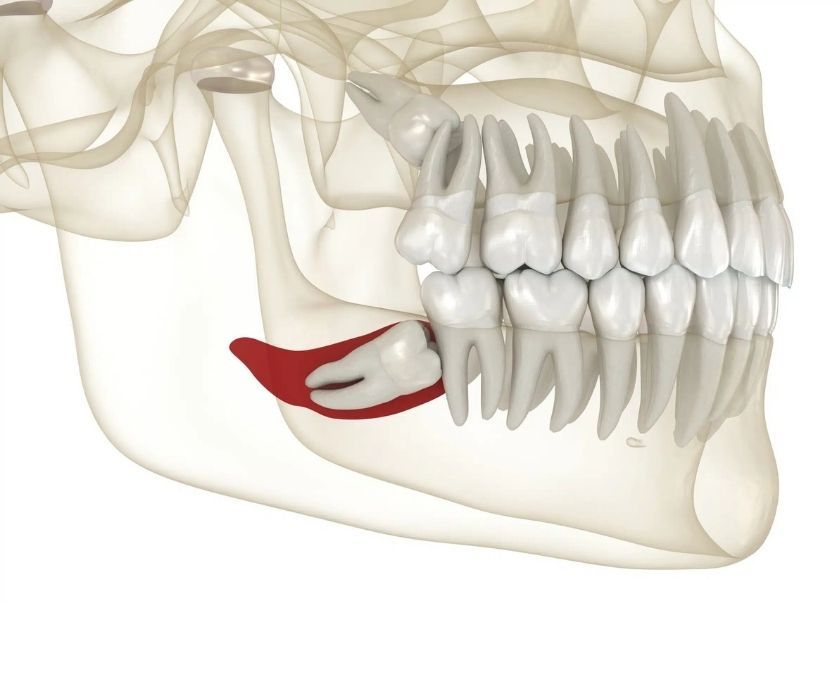

Răng khôn (răng số 8) là chiếc răng mọc cuối cùng trên cung hàm, thường xuất hiện khi chúng ta ở độ tuổi 17–25. Tuy nhiên, không phải chiếc răng khôn nào cũng mọc suôn sẻ. Trong nhiều trường hợp, răng khôn mọc kẹt (răng khôn mọc lệch, mọc ngầm) là tình trạng rất phổ biến – khi răng bị thiếu chỗ mọc, lệch hướng hoặc kẹt một phần trong nướu hoặc xương hàm, không thể trồi lên bình thường.

Trong một số trường hợp, răng khôn mọc ngầm gây áp lực lên xương hàm, hình thành nang quanh thân răng (dentigerous cyst). Nang này có thể phát triển, làm tiêu xương, biến dạng xương hàm và đe dọa các răng kế cận.

Tiêu xương và hình thành nang quanh răng khôn